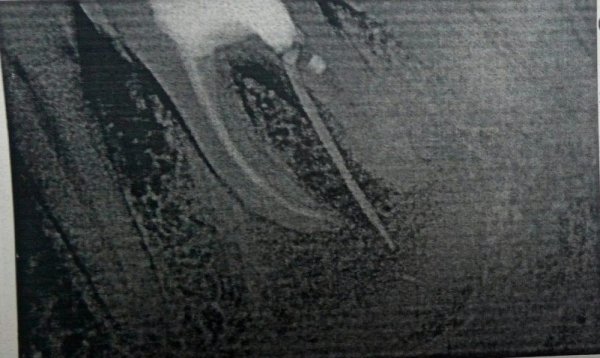

Семь лет назад лечил зуб, сделали хорошую пломбу, которая до сих пор держится, но на десне этой пломбы, два месяца назад, появился прыщик. Потом он превращался в шишку и со временем исчезал, и так много раз. Был сегодня у стоматолога в местной поликлинике, посмотрев снимки, сказала или удаляем, или оставляем. Если будет болеть, то приходи на удаление.

У вас обострение периодонтита (хроническое воспаление), дальше будет именно хуже, вплоть до удаления данного зуба. Необходимо обратиться к врачу, данная проблема лечится в несколько посещений и при неблагоприятном исходе, может затянуться на несколько месяцев.